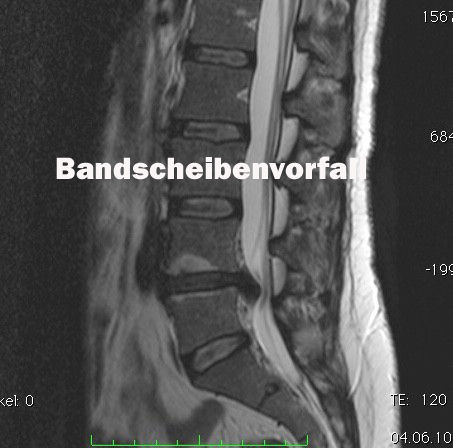

Der Bandscheibenvorfall an der Lendenwirbelsäule

Ein Bandscheibenvorfall entsteht, wenn der innere Gallertkern einer Bandscheibe durch den äußeren Faserring tritt und auf Nervenstrukturen drückt. Dies kann zu Schmerzen, Taubheitsgefühlen oder Lähmungen führen, abhängig von der Lage des Vorfalls. Zur Diagnose werden Anamnese, eine gründliche klinische Untersuchung sowie bildgebende Verfahren wie MRT eingesetzt. Die Therapie erfolgt in den meisten Fällen konservativ durch Schmerzmedikation, Physiotherapie und Schonung und gezielte Infiltrationen. Dies führt in 80-90% der Fälle zur Heilung. Helfen konservative Therapie nicht, dann kann ein Bandscheibenvorfall endoskopisch entfernt werden.